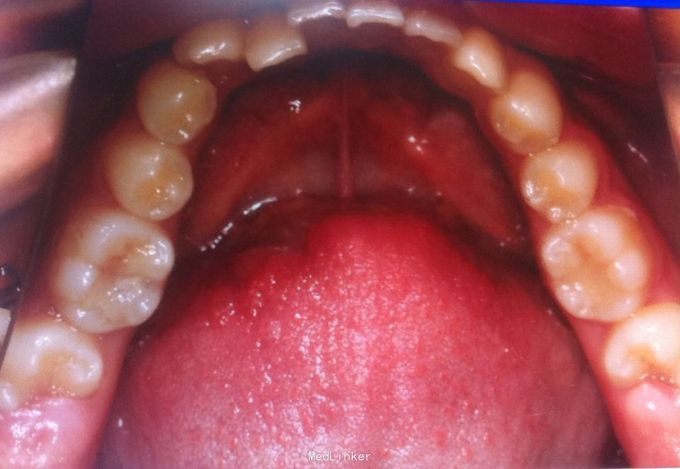

恒牙期 口内见摆式矫治器 左侧磨牙近中关系,右侧中性关系 前牙覆合覆盖正常 中线不正 上下牙列拥挤 张口度正常 关节有弹响 开口型异常

安氏三类 拆除摆式矫治器,清洁牙面,直丝弓矫治器,排齐整平上下牙列,矫治后磨牙中性关系,前牙覆合覆盖正常,维持现有面型